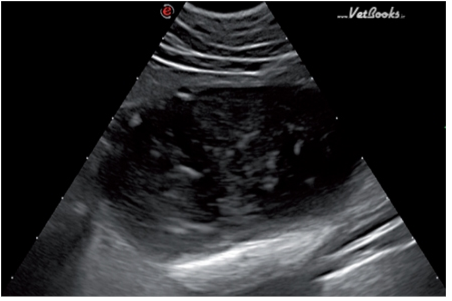

FLUTD的超声表现包括尿液的产回声性升高(图7),是因为膀胱内的细胞和蛋白含量增多。当发生尿道阻塞时,会看到尿道和膀胱的扩张(图8)。当尿道周围的脂肪发炎时会在尿道的周围看到少量游离液体(图9)。